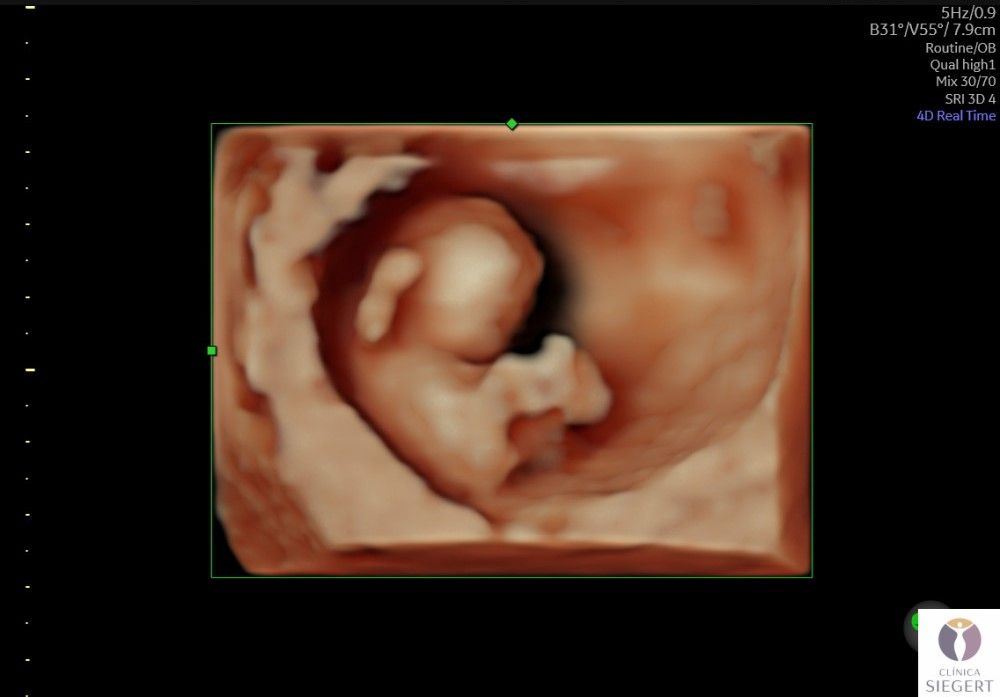

Nuevo ecógrafo de última generación con la mejor imagen 3D 4D 5D (edición en vivo: HD LIVE). ¡CONOCE A TU BEBÉ ANTES DE NACER! En Clínica Siegert, en Ibi